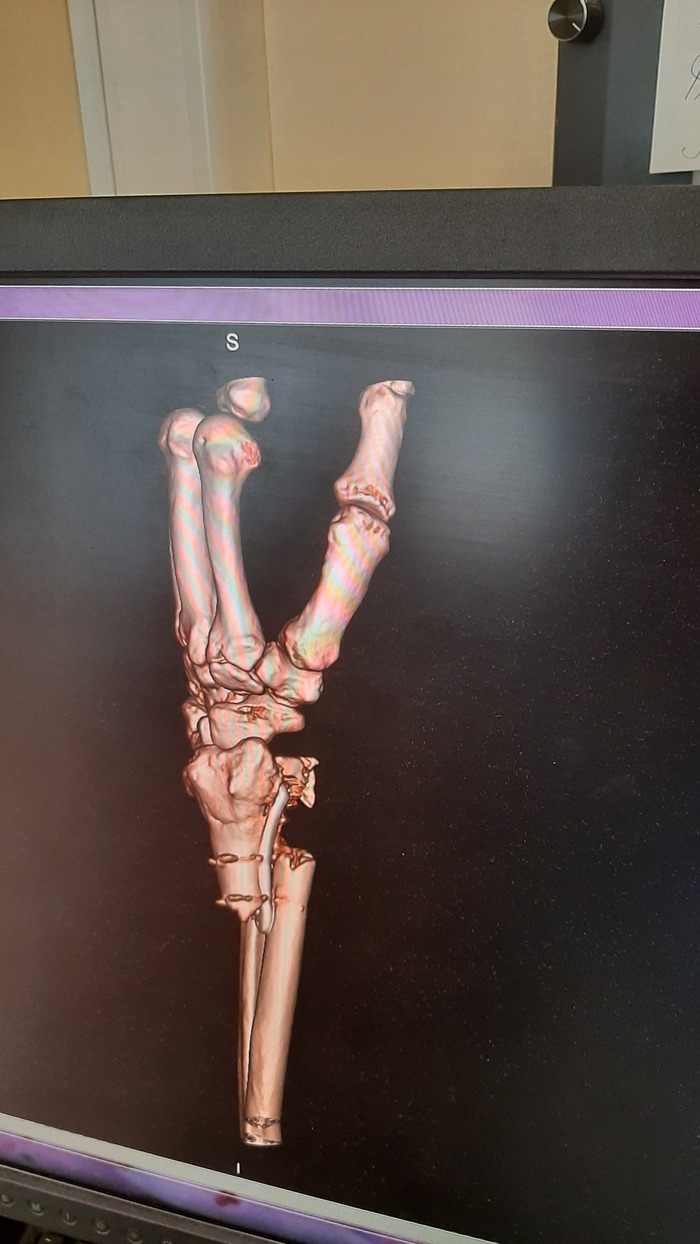

Ну и очень много рентгеновских снимков